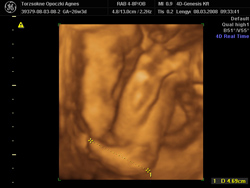

szuper babócaképek vannak

nagyon tetszenek. nekünk csuszik a 4D

kis keze

kis keze

kis lába

kis lába Azért remélem nálatok kicsit legalább sütött a nap!